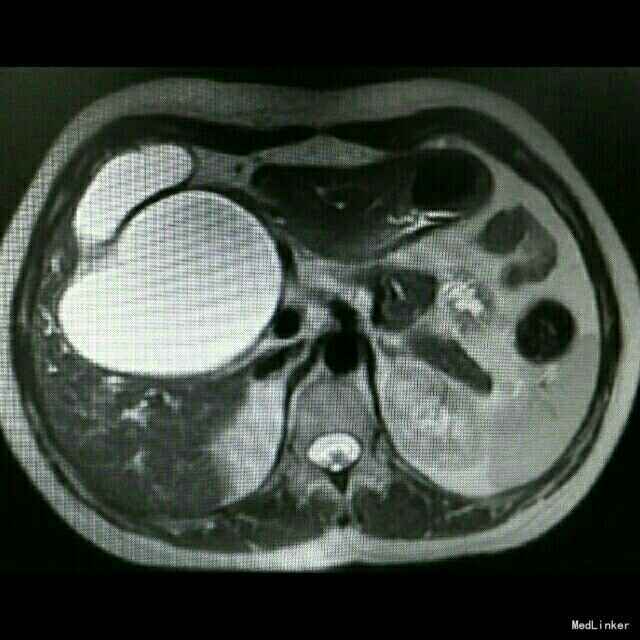

查体:皮肤巩膜轻度黄染 检查:B超示胆总管囊性占位,胆囊增大,肝内胆管扩张。MRCP:先天性肝外胆管囊肿,伴肝内胆管及胰管扩张,胆囊炎,右肝血管瘤可能。TB 65 umol/L;DB 41 umol/L; ALT 137U/L;AST74 U/L ;γ-GT366 U/L术后恢复正常。肿瘤指标正常。

诊断:先天性胆总管囊肿,慢性胆囊炎。 治疗:行胆总管囊肿切除+胆囊切除+胆道空肠Roux-en-y吻合术。术中腹腔未见积液,胆总管大小越25*8.5cm,囊壁较厚,胰头部受压明显,胆囊10*6*5cm。沿胆囊底打开胆囊浆膜,逆行游离至胆囊管汇入处,结扎胆囊动脉,打开肝十二指肠韧带,沿胆总管囊肿游离囊肿,保护肝动静脉及门静脉,向下游离至胰内胆管,于囊肿下端切断胆总管,结扎残端。向上游离至肝门部,于左右肝管汇合处离断,完整切除囊肿。距屈氏韧带25cm直线闭合器断空肠,游离远端空肠系膜行肝总管远端空肠段侧吻合。距胆肠吻合口远端45cm处,空肠与近端空肠残端以直线切割闭合行空肠侧侧吻合。间断缝合残端,吻合口放置引流管,关腹。术后加强白蛋白对症支持治疗,术后第5日开始进食流质。病理回报慢性胆囊炎。